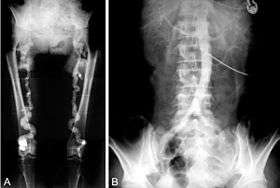

Often Mönckeberg’s arteriosclerosis is discovered as an incidental finding in an X-ray radiograph, on mammograms, in autopsy, or in association with investigation of some other disease, such as diabetes mellitus or chronic kidney disease. Typically calcification is observed in the arteries of the upper and lower limb although it has been seen in numerous other medium size arteries.[5] In the radial or ulnar arteries it can cause "pipestem" arteries, which present as a bounding pulse at the end of the calcific zone. It may also result in "pulselessness." Epidemiological studies have used the ratio of ankle to brachial blood pressure (ankle brachial pressure index, ABPI or ABI) as an indicator of arterial calcification with ABPI >1.3 to >1.5 being used as a diagnostic criterion depending on the study.[8][9]